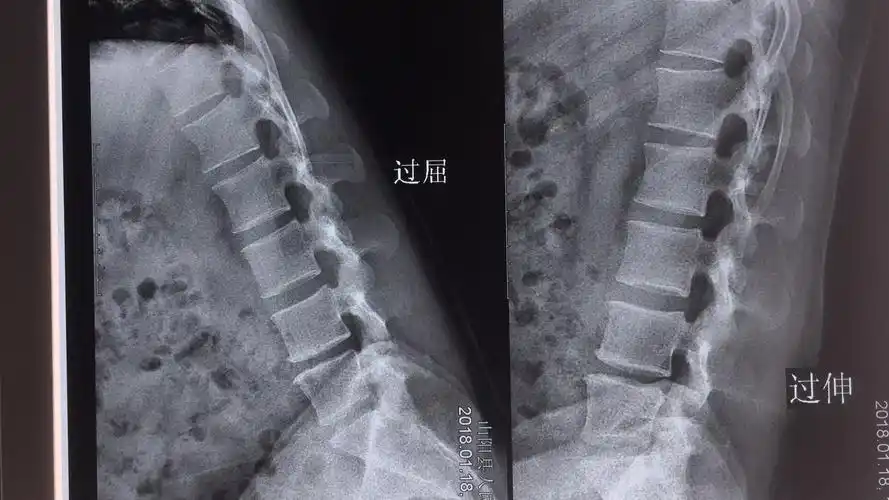

医影技术丨腰椎六位片摄影技术——正侧位,双斜位,过伸过屈位_平台